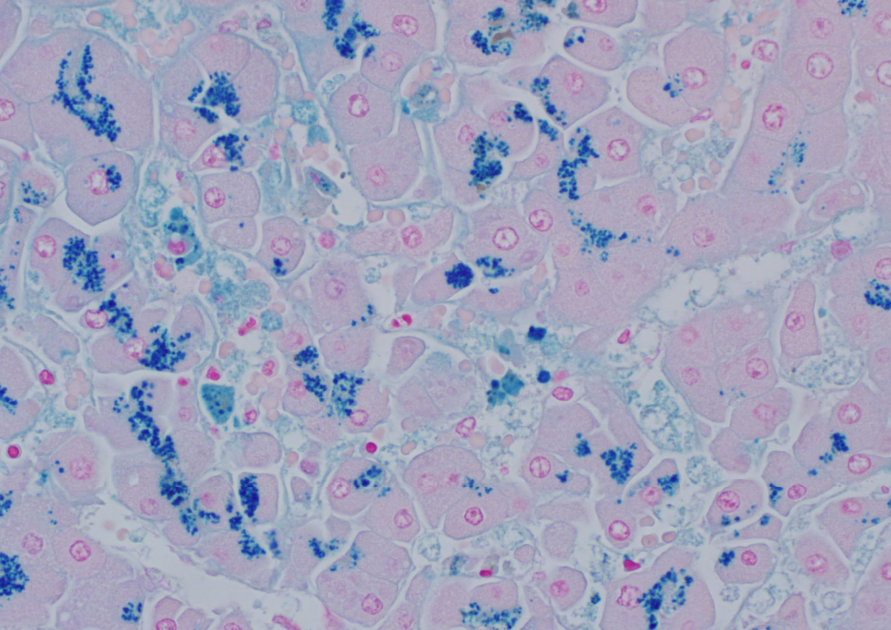

Special stain for Wilsons disease

Rhodanine- stains for copper

Special stain for Iron disease storage- what diseases does this include?

Prussian blue

Hemochromatosis, hemosiderosis